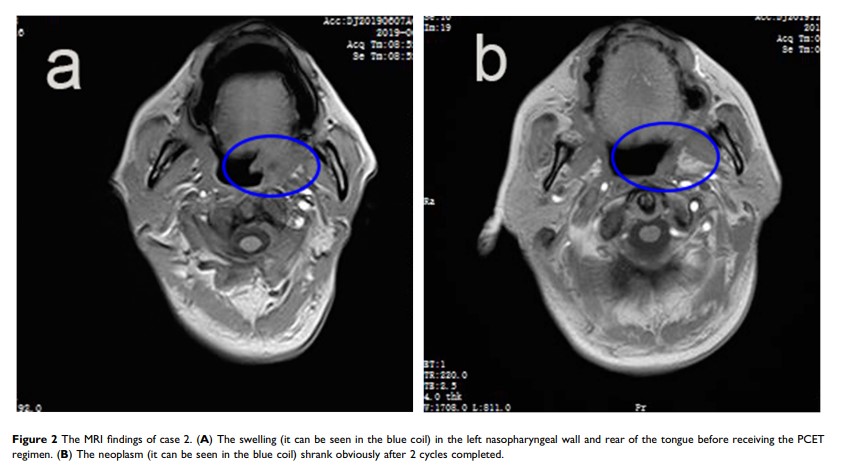

使用 PD-1 抗体、西达本胺、依托泊苷和沙利度胺(PCET)有效治疗复发/难治性自然杀手/T 细胞淋巴瘤:关于三个病例的报告